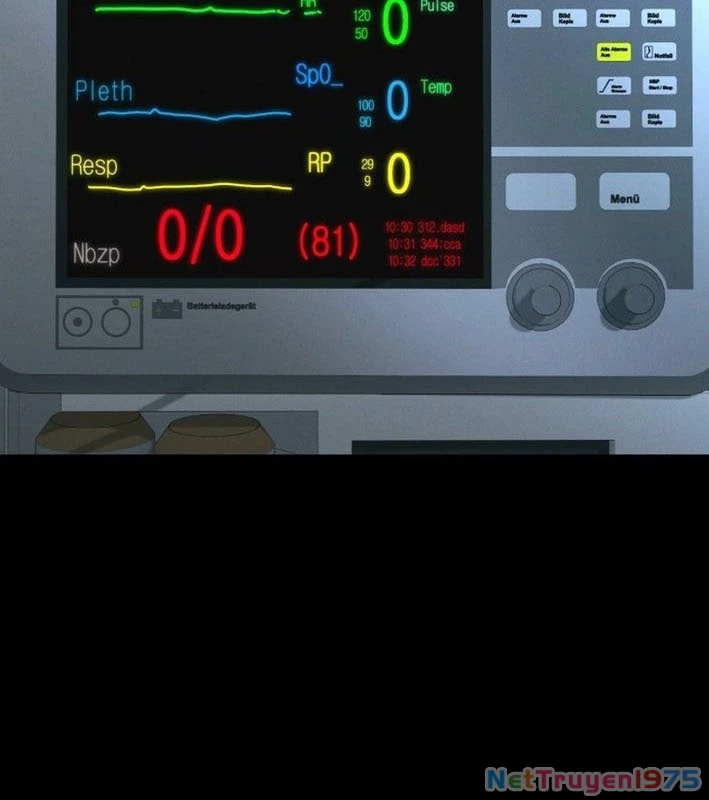

Kẻ Chôn Cất Quái Vật - Chapter 1